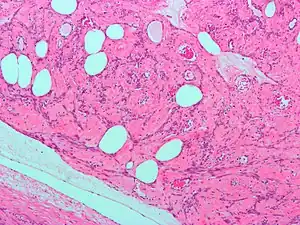

| Uterine lipoleiomyoma, a type of leiomyoma. H&E stain. | |

A rare form of these tumors is uterine lipoleiomyoma—benign tumors consisting of a mixture of adipocytes and smooth muscle cells. Uterine lipoleiomyomata have been observed together with ovarian and other pathologies and some of them may develop into liposarcoma.[2][3] These tumors are monoclonal, and non-random chromosomal abnormalities have been seen in 40% of the tumors.